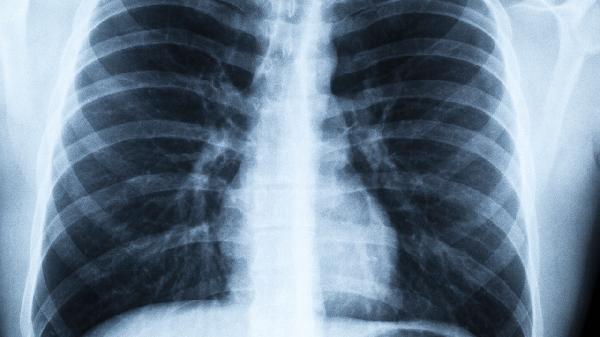

肺炎咳嗽的孩子飲食需要注重清淡、營養(yǎng)均衡,同時選擇具有潤肺止咳、增強免疫的食物,例如梨、白蘿卜粥和瘦肉湯等。適當(dāng)?shù)娘嬍痴{(diào)理可輔助緩解癥狀,加速康復(fù),但如果病情嚴(yán)重或久治不愈,應(yīng)及時就醫(yī)。